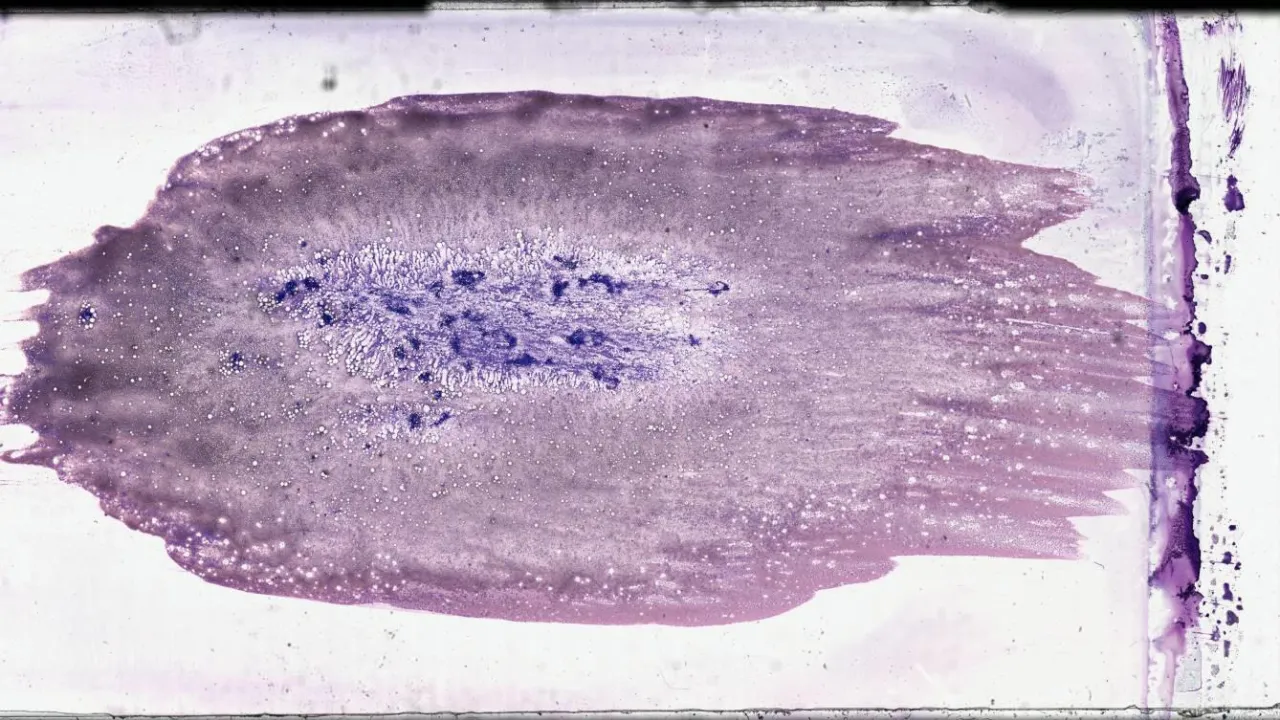

Bone Marrow, Acute myeloid leukemia, aspirate